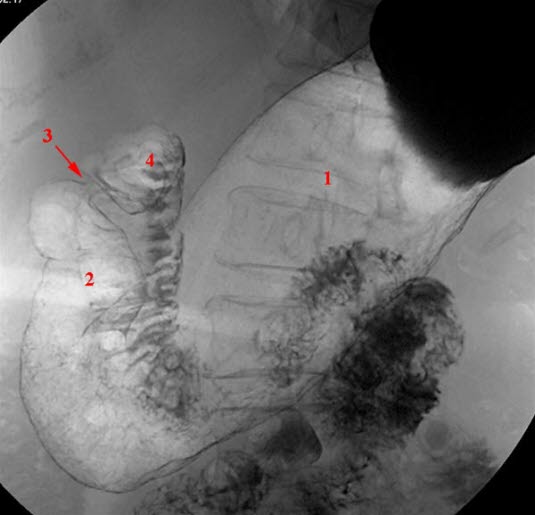

Dobbelkontrast-teknikk med barium og luft, pasienten i ryggleie

- Corpus ventriculi (magesekk)

- Antrum pyloricum

- Pylorus

- Bulbus duodeni (Tolvfingertarm)